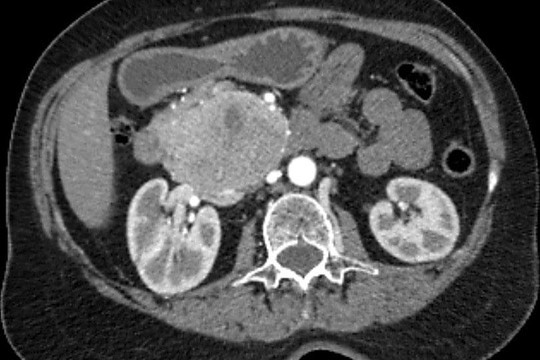

«Միքայելյան» համալսարանական հիվանդանոցում հերթական բարդ վիրահատությունն է իրականացվել, հեռացվել է ենթաստամոքսային գեղձի գլխիկի մեծ ուռուցք ավելի քան 10սմ տրամագծով, որը սերտ հպված էր միջընդերային զարկերակին և երակին:

Առհասարակ ենթաստամոքսային գեղձի գլխիկի մեծ չափի ուռուցքները համեմատաբար քիչ են հանդիպում: Առավել քիչ են հանդիպում այն դեպքերը, երբ գեղձի գլխիկի մեծ չափերի ուռուցքը չի առաջացնում մեխանիկական դեղնուկ: Համալսարանական հիվանդանոցի Վիրաբուժության կլինիկա է դիմել 62 տ. կին՝ գանգատվելով ցավից և ծանրության զգացումից վերորովայնային (էպիգաստրալ) շրջանում:

Կատարվել է պանկրեատոդուոդենալ մասնահատում, տեխնիկական դժվարություններով ուռուցքն անջատվել է վերին միջընդերային երակից և զարկերակից:

Հեռացված հյուսվածքի հետազոտությամբ հայտնաբերվել է ենթաստամոքսային գեղձի գլխիկի նեյրոէնդոկրին ուռուցք: